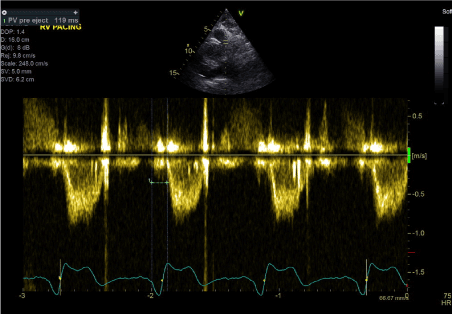

The final stage was to optimise the pacemaker settings to achieve fusion beats while pacing in DDD mode. We achieved this by programming the paced AV delay to 180 ms and sensed AV delay to 160 ms. The result was fusion beats pacing with QRS duration of 110-115 ms (Figures 2 and 3). Transthoracic echocardiography showed improvement of LV systolic function with normal septal motion. The LV-PEP and RV-PEP measured at this stage were almost identical with LVPEP measuring 159 ms and RVPEP measuring 156 ms (Figures 10 and 11).  The resulting IVMD was 3 ms confirming synchronous LV and RV contractions.

Figure 10. LV-PEP measurement in fusion beats rhythm (PW Doppler in LVOT)

Figure 11. RV-PEP measurement in fusion beats rhythm (PW Doppler in RVOT)